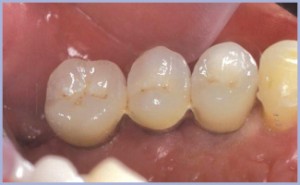

Si eseguono protesi su pilastro naturale e su impianti, non collegate (figg. 30-32).

Per completare il trattamento viene eseguita una coronoplastica in composito a mascheramento della recessione gengivale e a chiusura del diastema (figg. 33-34).